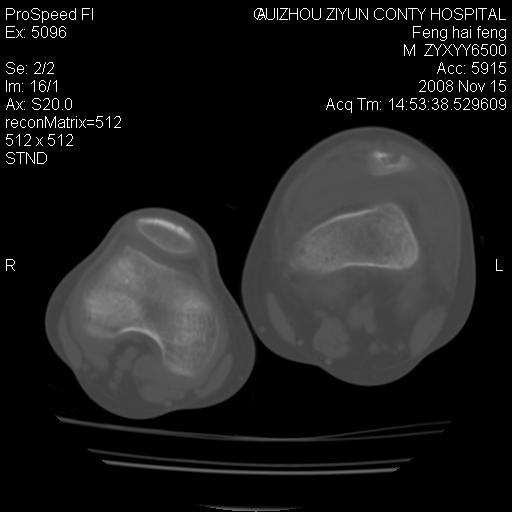

标题: CT16656:M 14Y 左膝关节肿胀一年余。其余病史不详。 [打印本页]

标题: CT16656:M 14Y 左膝关节肿胀一年余。其余病史不详。

考虑左侧髌骨结核;左膝关节滑膜肿胀、增厚,关节囊积液。

左膝滑膜型关节结核可能性大!支持!滑膜型关节结核主要ct表现:关节囊肿胀,积液,关节面见小破坏灶,并见点状死骨!

好大的左腿!考虑左侧髌骨结核,左膝关节滑膜肿胀、增厚,关节囊积液。

左侧髌骨结核;左膝关节滑膜肿胀、增厚,关节囊积液